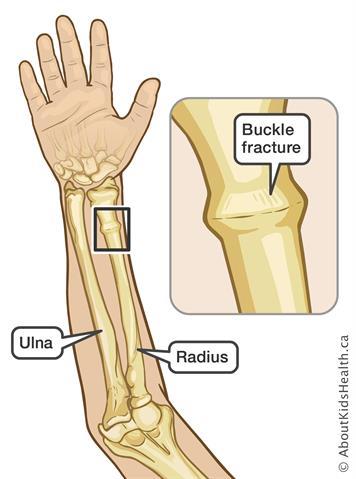

Torus fracture?

Buckle fracture of radius

Greenstick fracture?

concave, cortex intact or buckled.